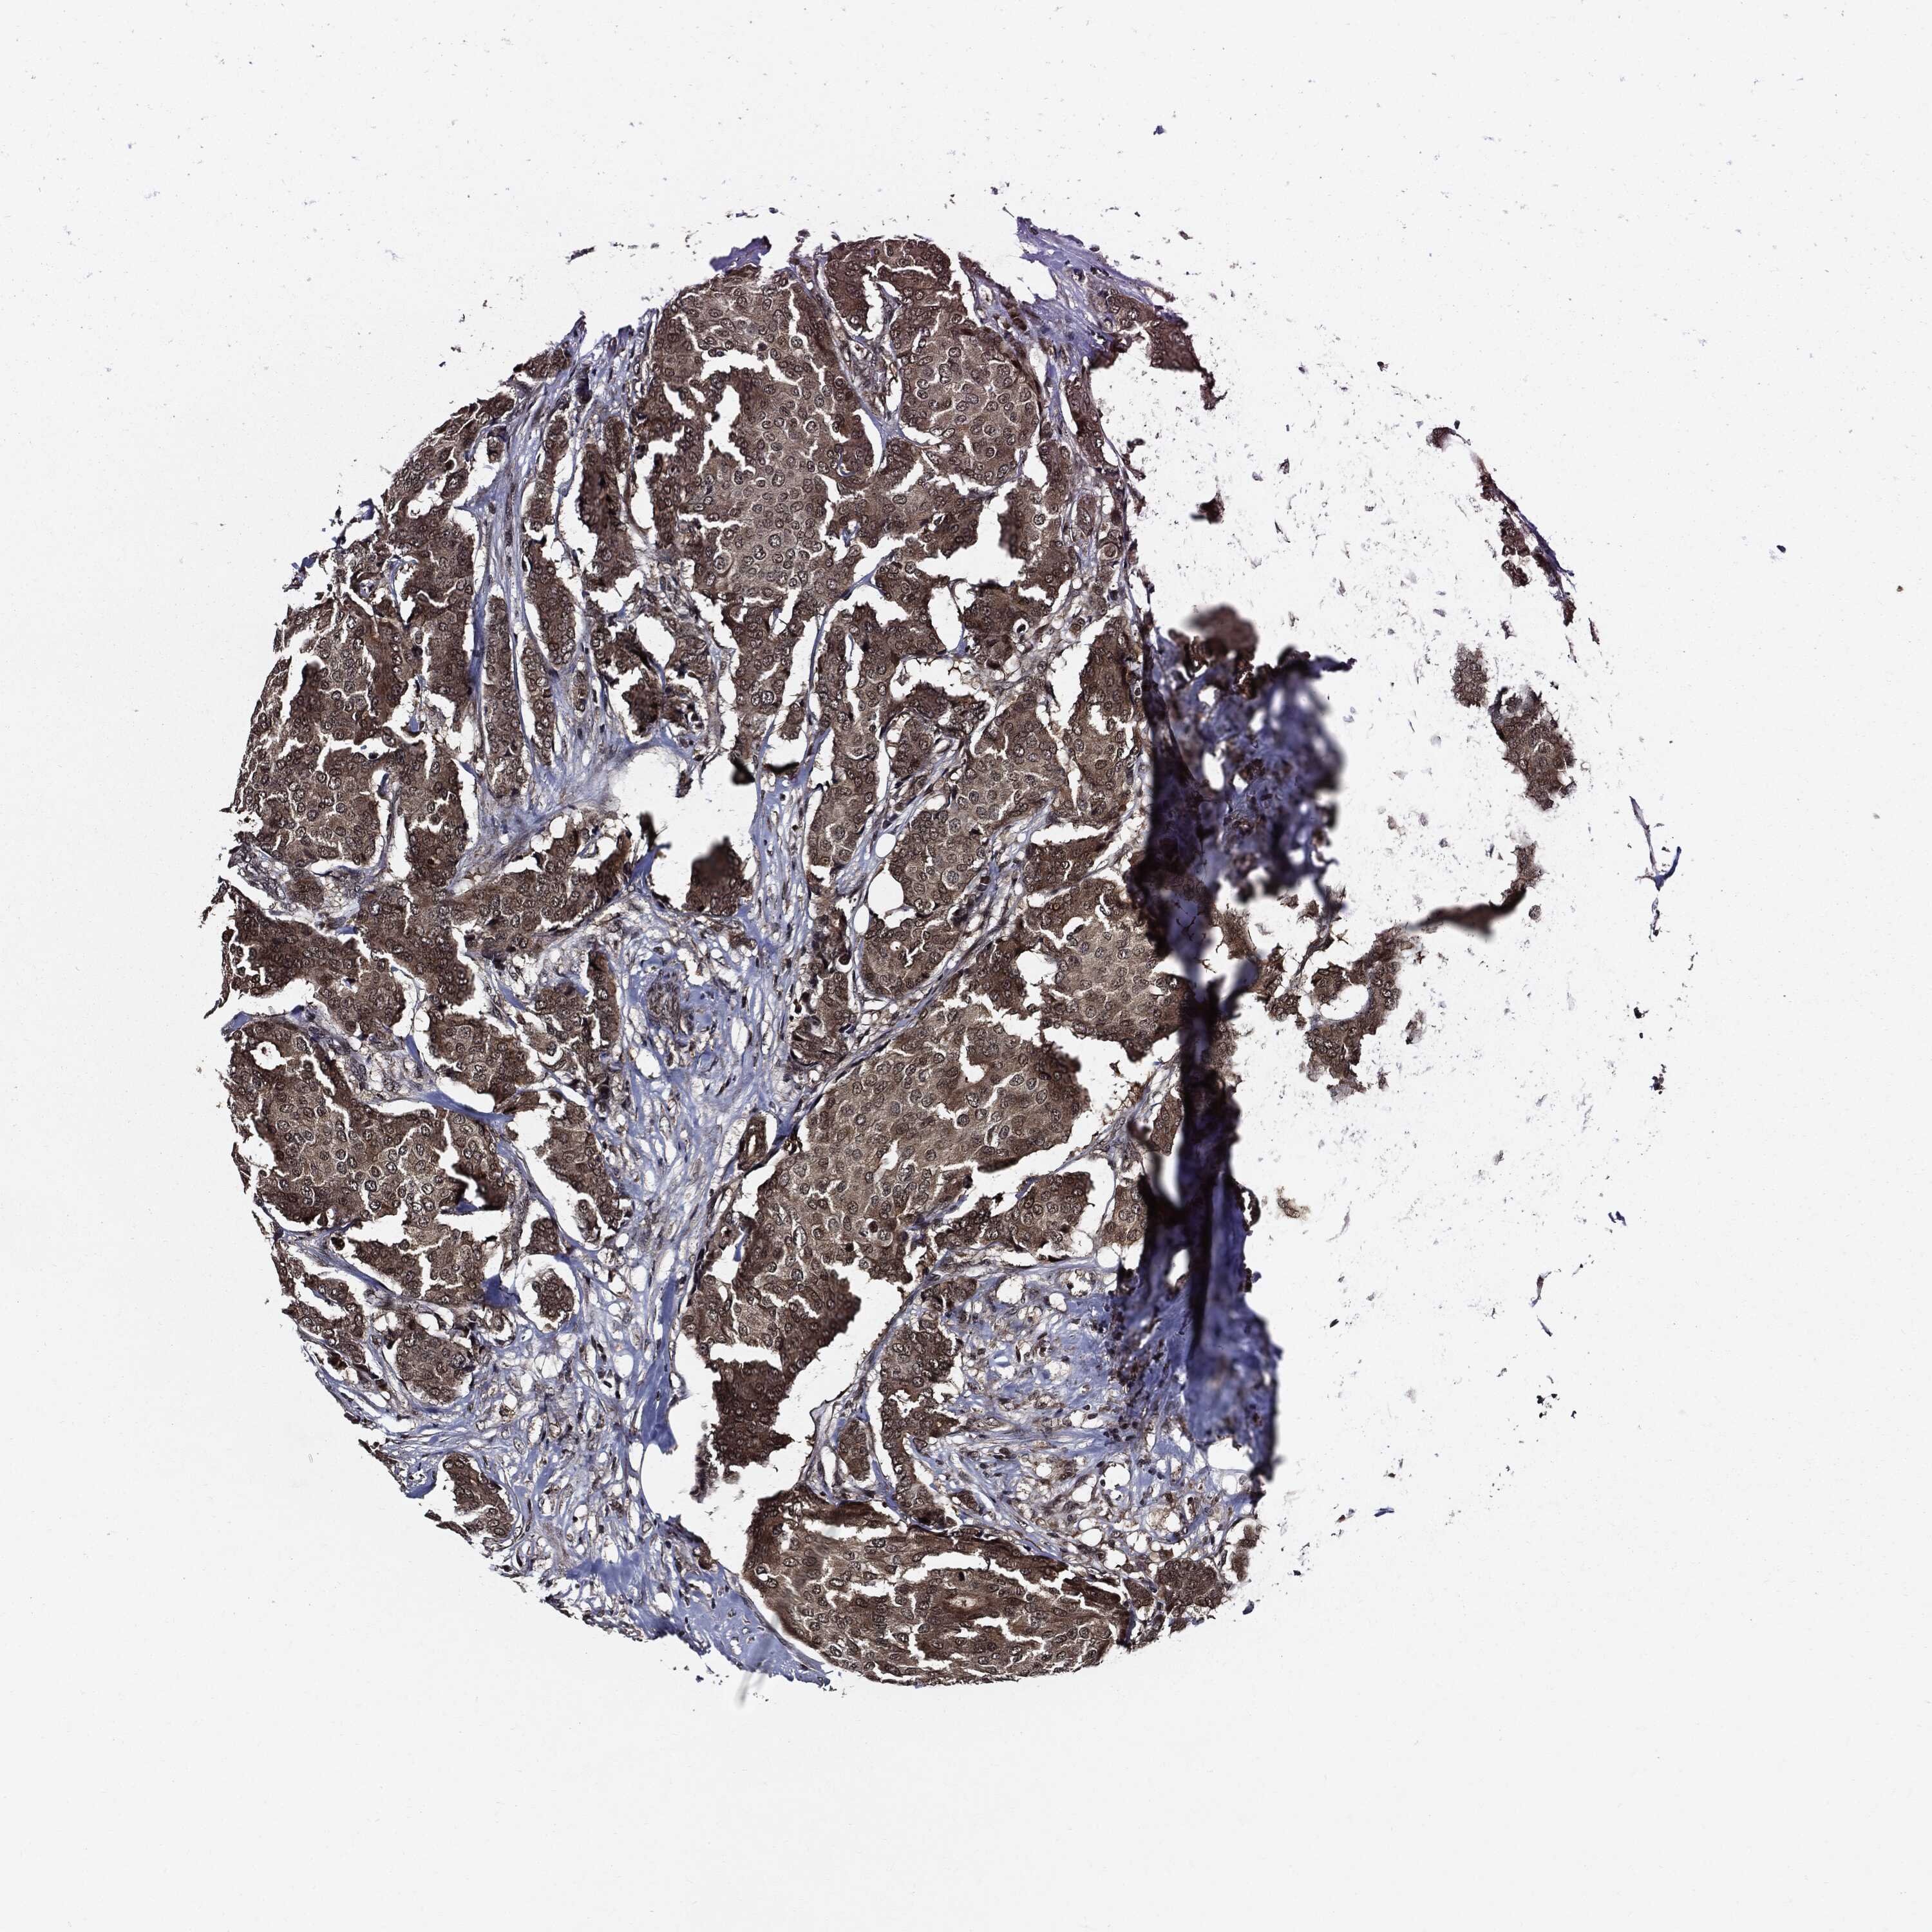

BRCA TCGA BRCA VALIDATION PROTEIN EXPRESSION

ANTIBODIES

AND

VALIDATION